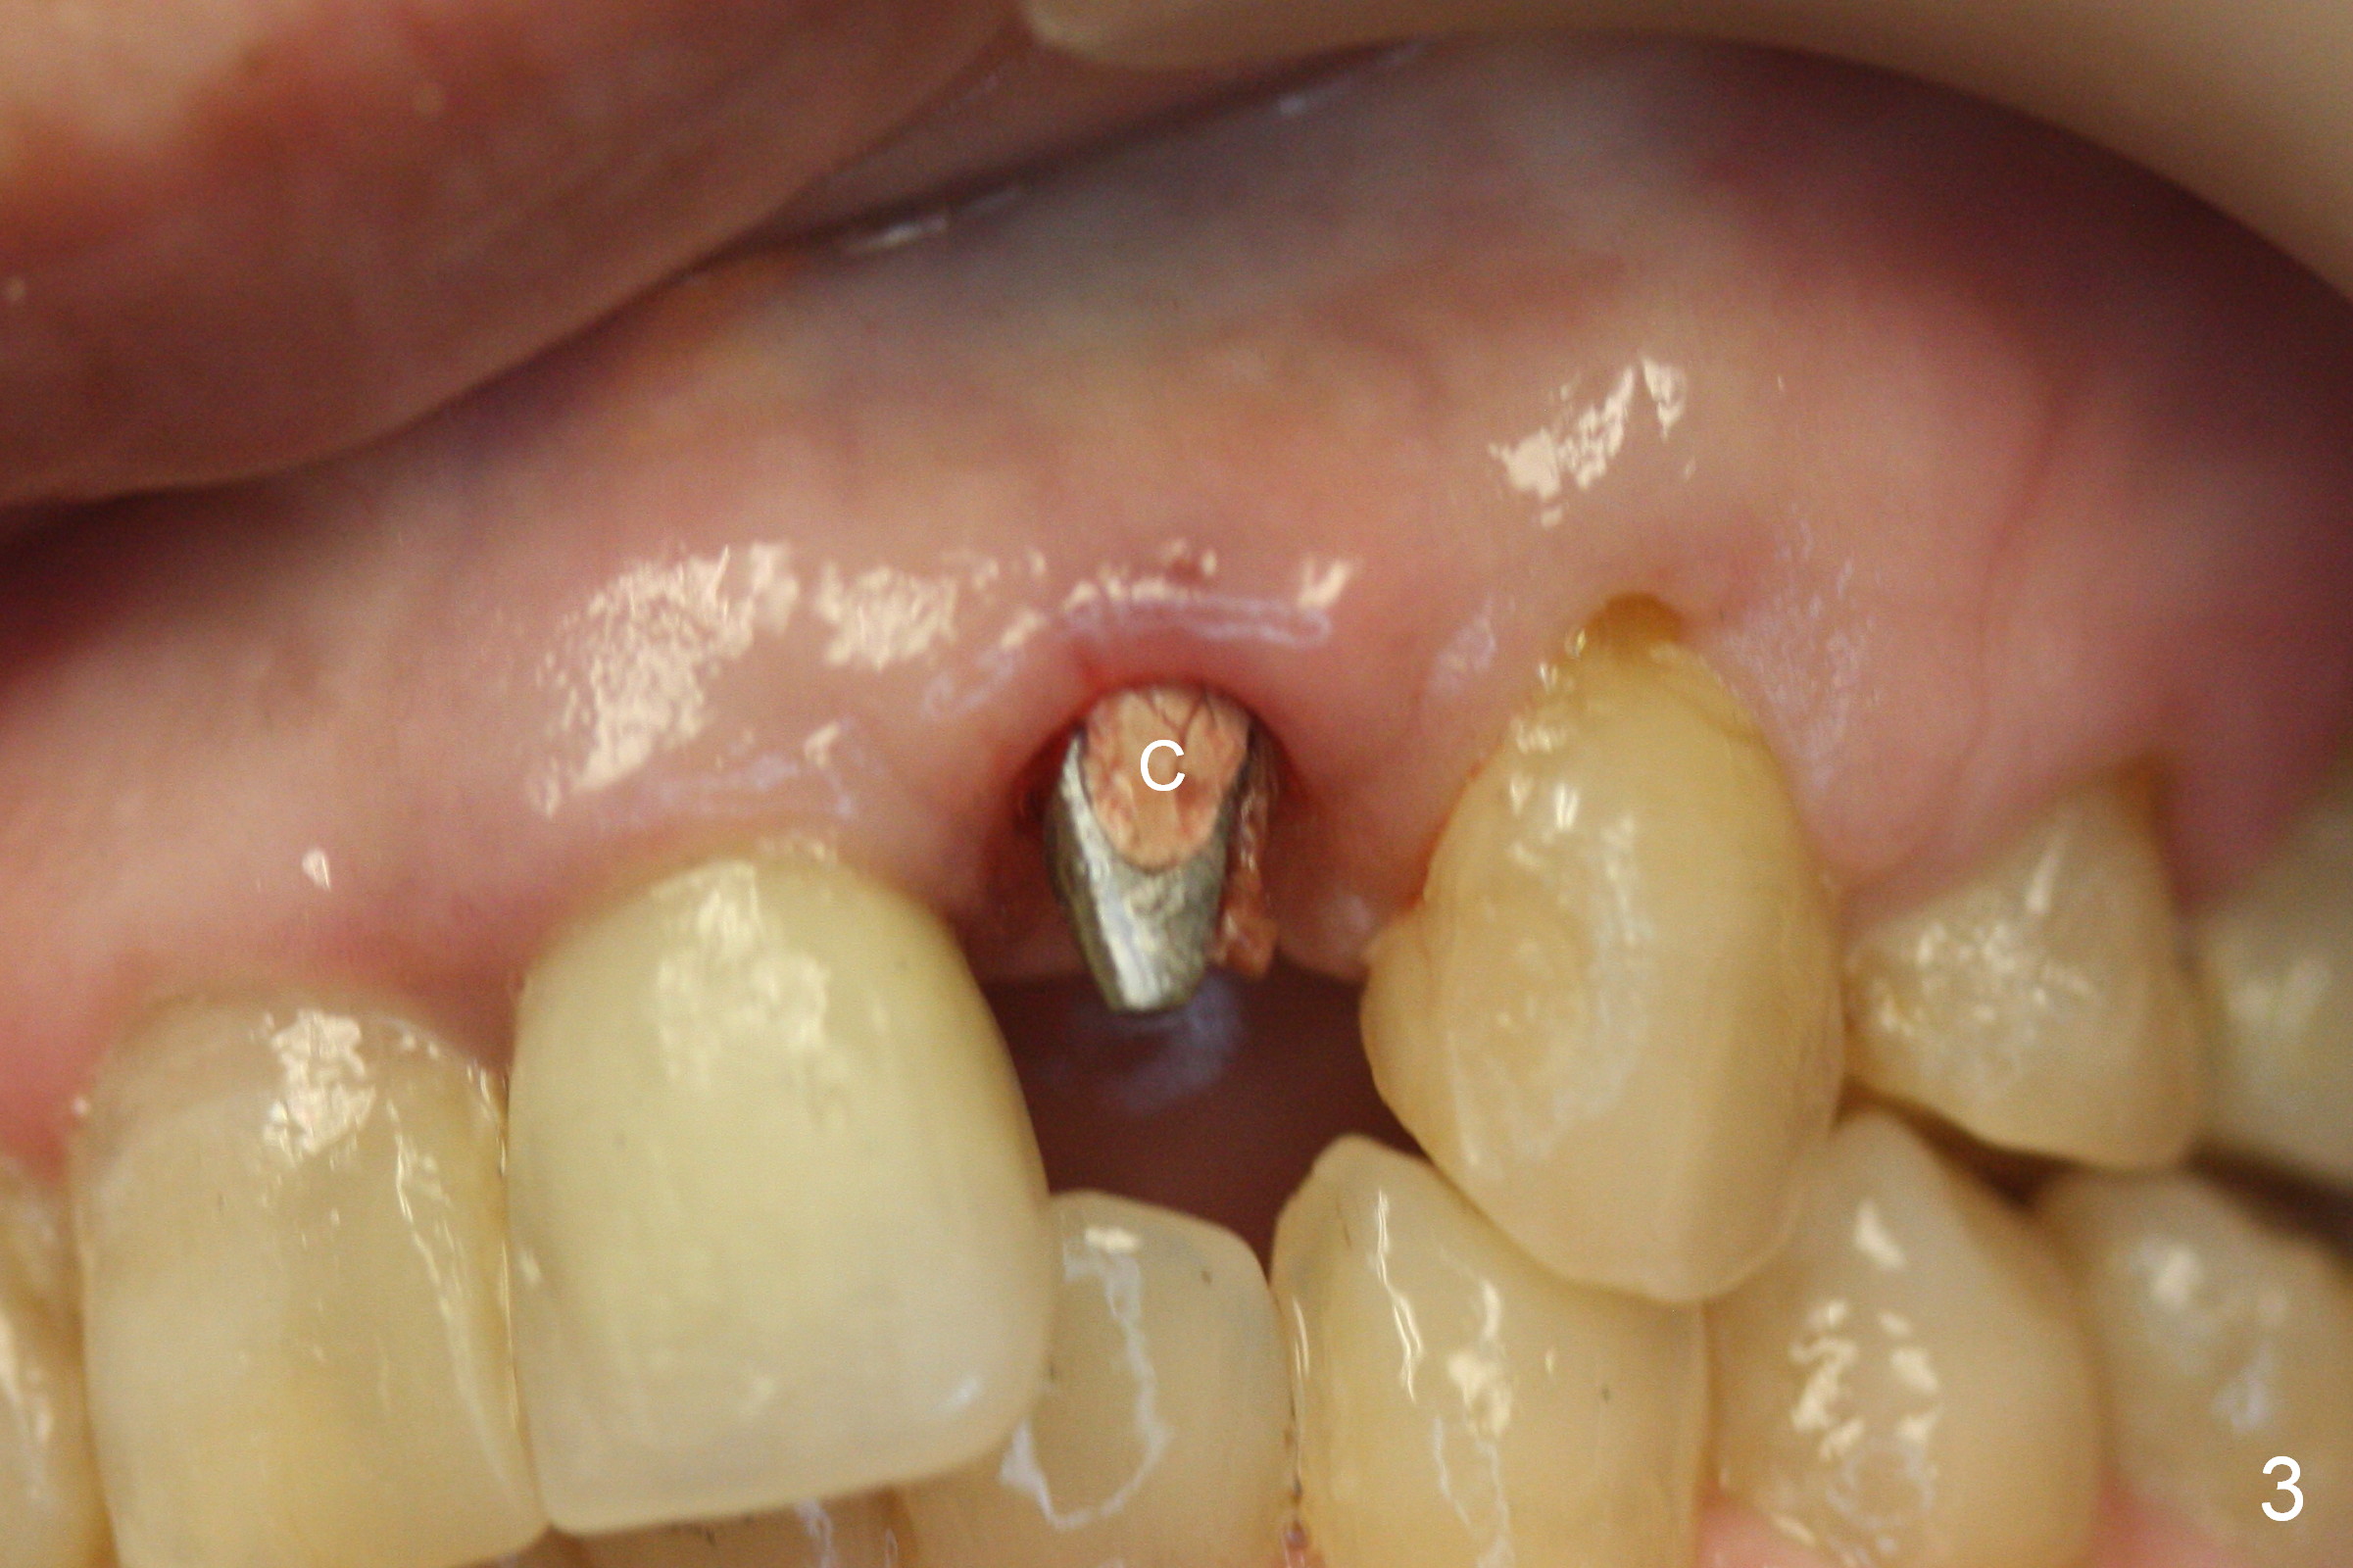

Placement of implant at the site of #10 is complicated. The trajectory is not ideal. Even though a 25 ° angled abutment is used, the abutment is still too buccal. Since the implant is placed deep (Fig.1,2), the margin is high (Fig.3). The margin of the crown should be thin and able to cover the Cavit as much as possible (Fig.3 C).

Fig.1,2 show the abutment (A) before and after torquing, respectively. After the torquing, the abutment turns mesially (Fig.2 white arrow) and apparently ascends slightly (black arrow).